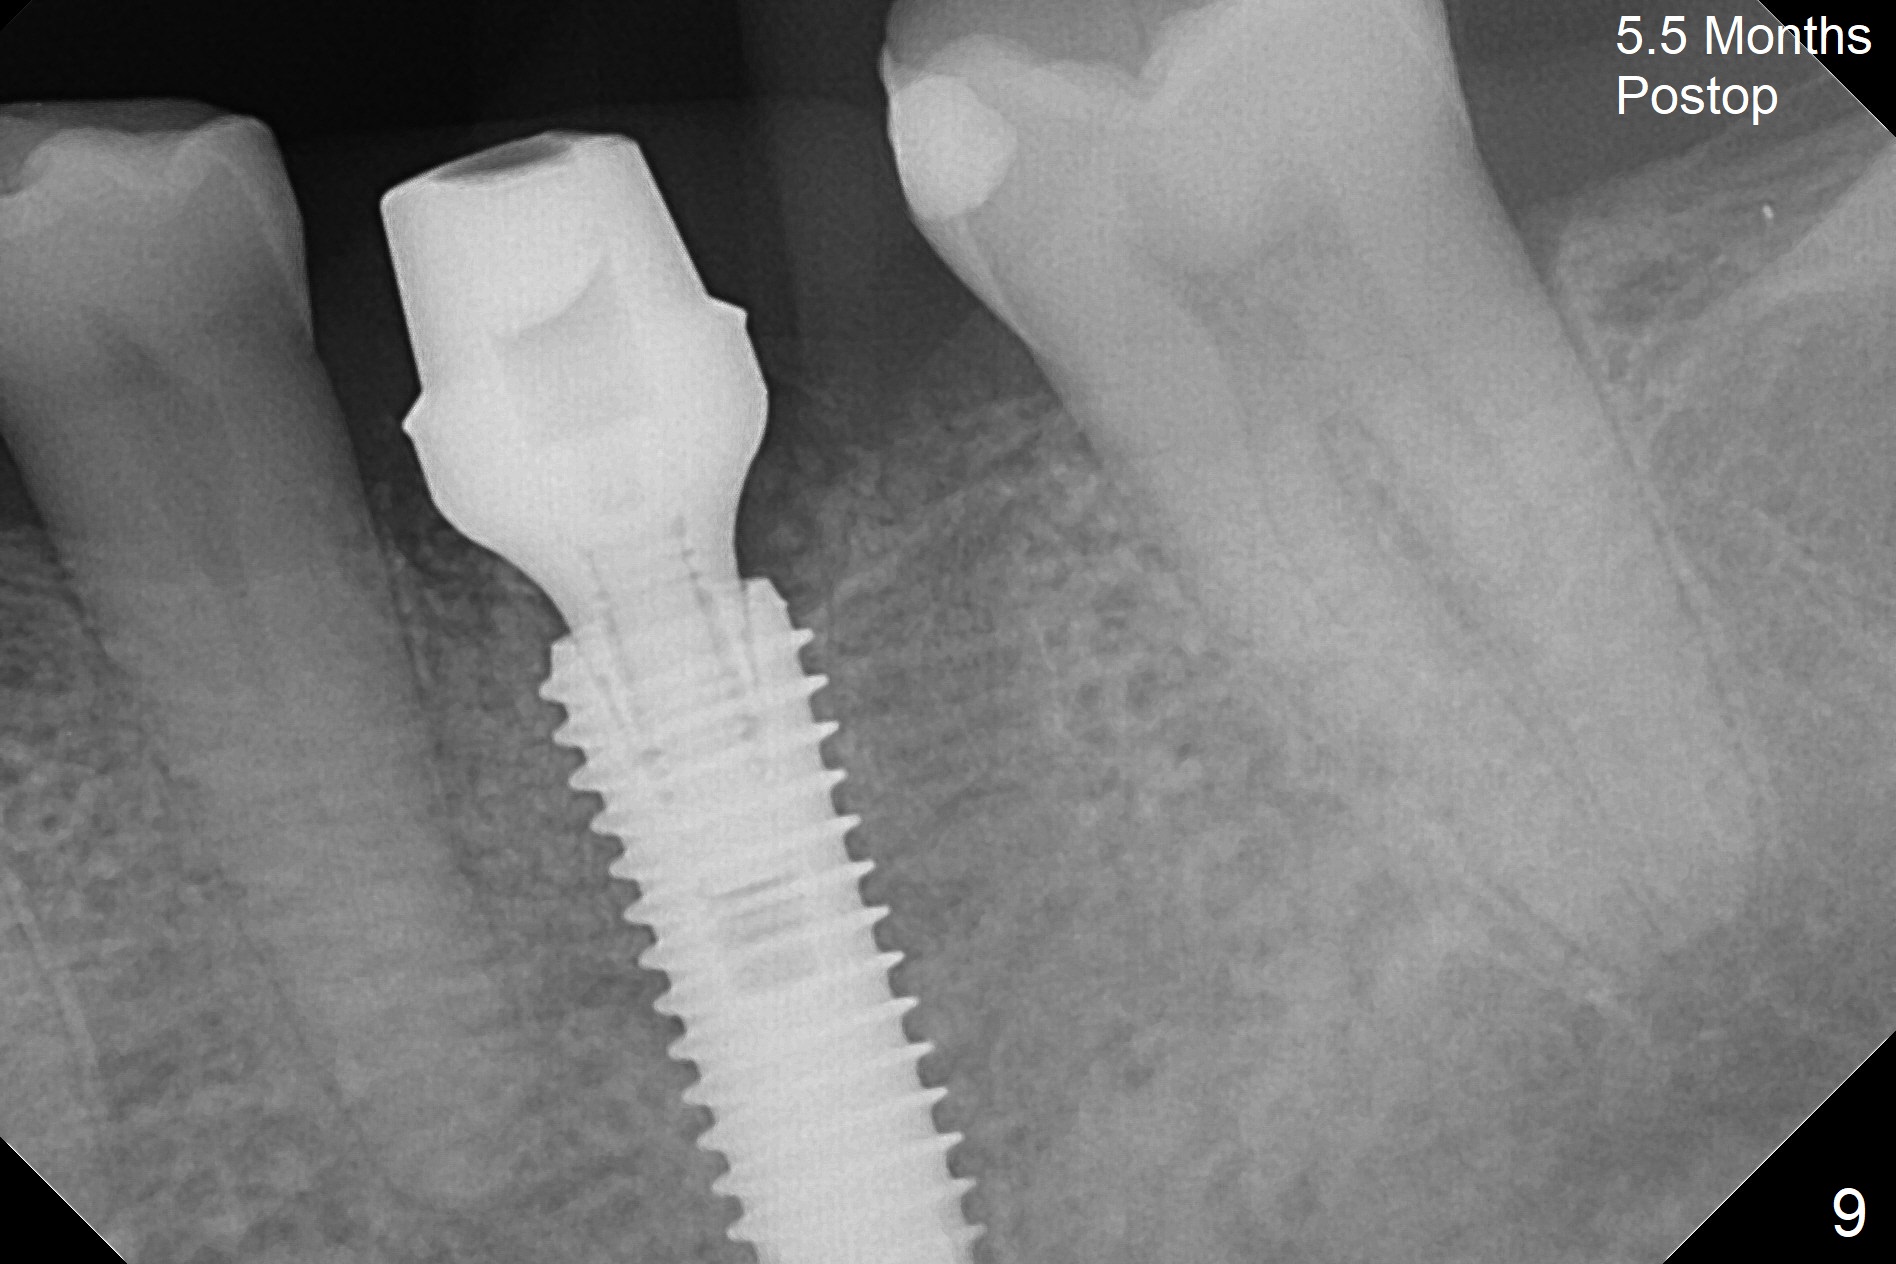

When the patient returns 9 months later, there is severe buccal gingival recession and abscess at #19 (Fig.1 *) with large mesial periradicular radiolucency (Fig.2 *).  The septum is thin and the buccal crest is low after extraction (Fig.3 * (mesial root vertical fracture)).  Osteotomy is initiated in the mesial socket immediately against the septum (Fig.4.5) with ~ 5 mm in the native bone.  Due to severe buccal plate resorption, a shorter implant is placed (Fig.6; 5x15 mm in stead of 18 mm).  There is at least 2 mm gap buccally for Vanilla Graft, which is also placed next to the implant and the neighboring root (Fig.7 *).  There is clearance from the Inferior Alveolar Canal (Fig.8 red dashed line).  Both the mesial and distal sockets heal 5.5 months postop (Fig.9), although the apical portion of the distal socket was not filled with allograft (Fig.7).  The implant was placed mesial.  The straight abutment (6.5x4(4) mm) (Fig.10) is changed to an angled one (5.5 x15 degrees 3 mm cuff (Fig.11)) before impression.  The implant is also placed buccally.  Therefore the implant position is far more important than its length.  The abutment is retightened 2.5 months post cementation, which is related to mesiobuccal placement of the implant (Fig.12).  An ideal trajectory is determined by drawing 2 horizontal lines (at crestal and apical levels: red lines in Fig.13), finding a central point of each line (vertical short line) and joining these 2 central points (Fig.14 pink line).  In fact the ideal osteotomy should have been established distal to the septum in this case.  Guided surgery may alleviate the issue.  The crown is not loose, but the patient feels that the implant tooth cannot sustain mastication.  In fact the screw is removed with hand driver (not wrench).  The abutment hex is rounded and worn.  A new 5.5x4(4) mm abutment is placed (without knowledge of previous use of an angled abutment) with mesial reduction to reduce undercut and buccodistal margin lowered to reduce gingival embrasure. It is that the straight abutment could decrease the chance of screw loosening.  Otherwise the implant has to be removed for better trajectory.